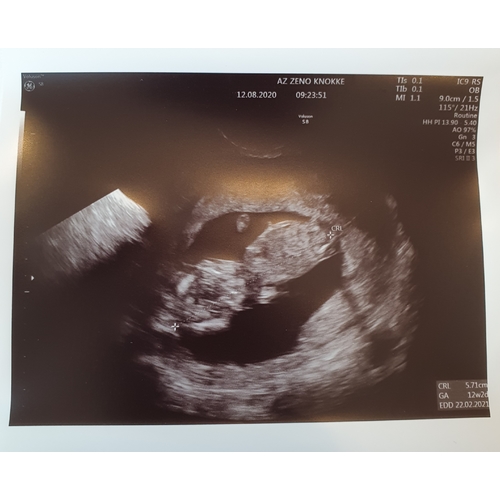

Dit was mn 12 weken echo 😅

Nu al eigenwijs ding dus ze zal wel echt van mij zijn vrees ik